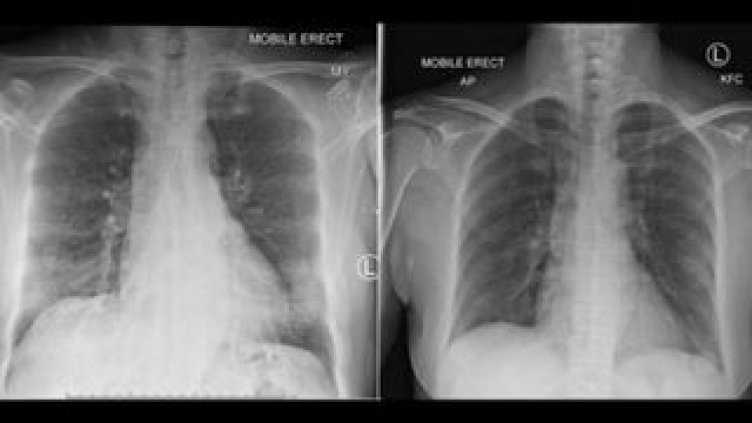

В зависимост от тежестта и фазата на заболяването, има различен тип засягане на белите дробове. Лекарят показа какво е то при пациент с лека клинична картина, без придружаващи заболявания и вече с два отрицателни теста за коронавирус.